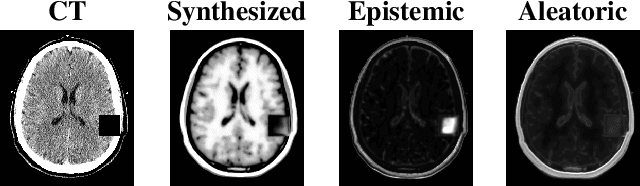

Abstract:Medical images are increasingly used as input to deep neural networks to produce quantitative values that aid researchers and clinicians. However, standard deep neural networks do not provide a reliable measure of uncertainty in those quantitative values. Recent work has shown that using dropout during training and testing can provide estimates of uncertainty. In this work, we investigate using dropout to estimate epistemic and aleatoric uncertainty in a CT-to-MR image translation task. We show that both types of uncertainty are captured, as defined, providing confidence in the output uncertainty estimates.